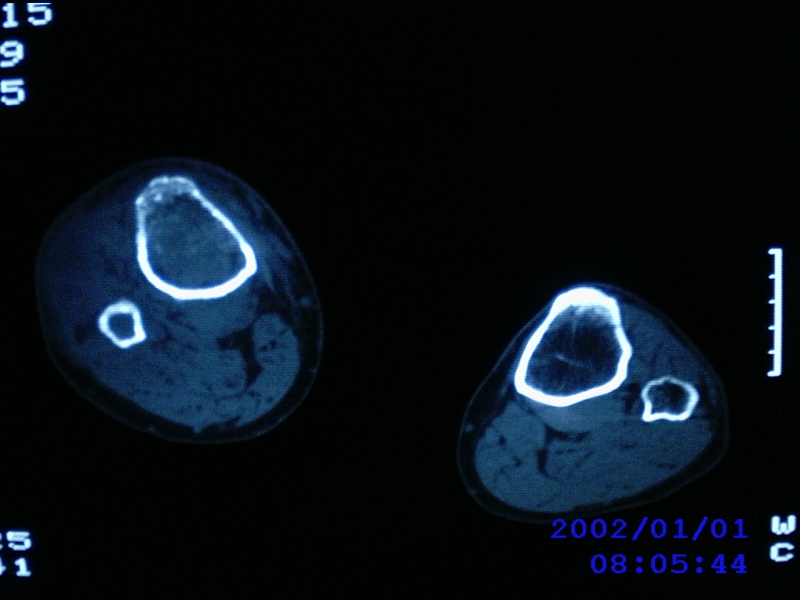

患者,男性,57岁,右侧膝关节疼痛伴肿脹10余年,加重一个月。

关节积液,关节间隙变窄,边缘骨破坏。考虑膝关节tb

关节积液,关节间隙变窄,骨质疏松,多发骨破坏,边缘轻度硬化,近端胫腓骨髓腔软组织充填,患者病史较长,支持考虑结核

有皮质的破坏~有死骨存在

多发骨破坏,骨质疏松,关节积液。考虑右膝关节结核。